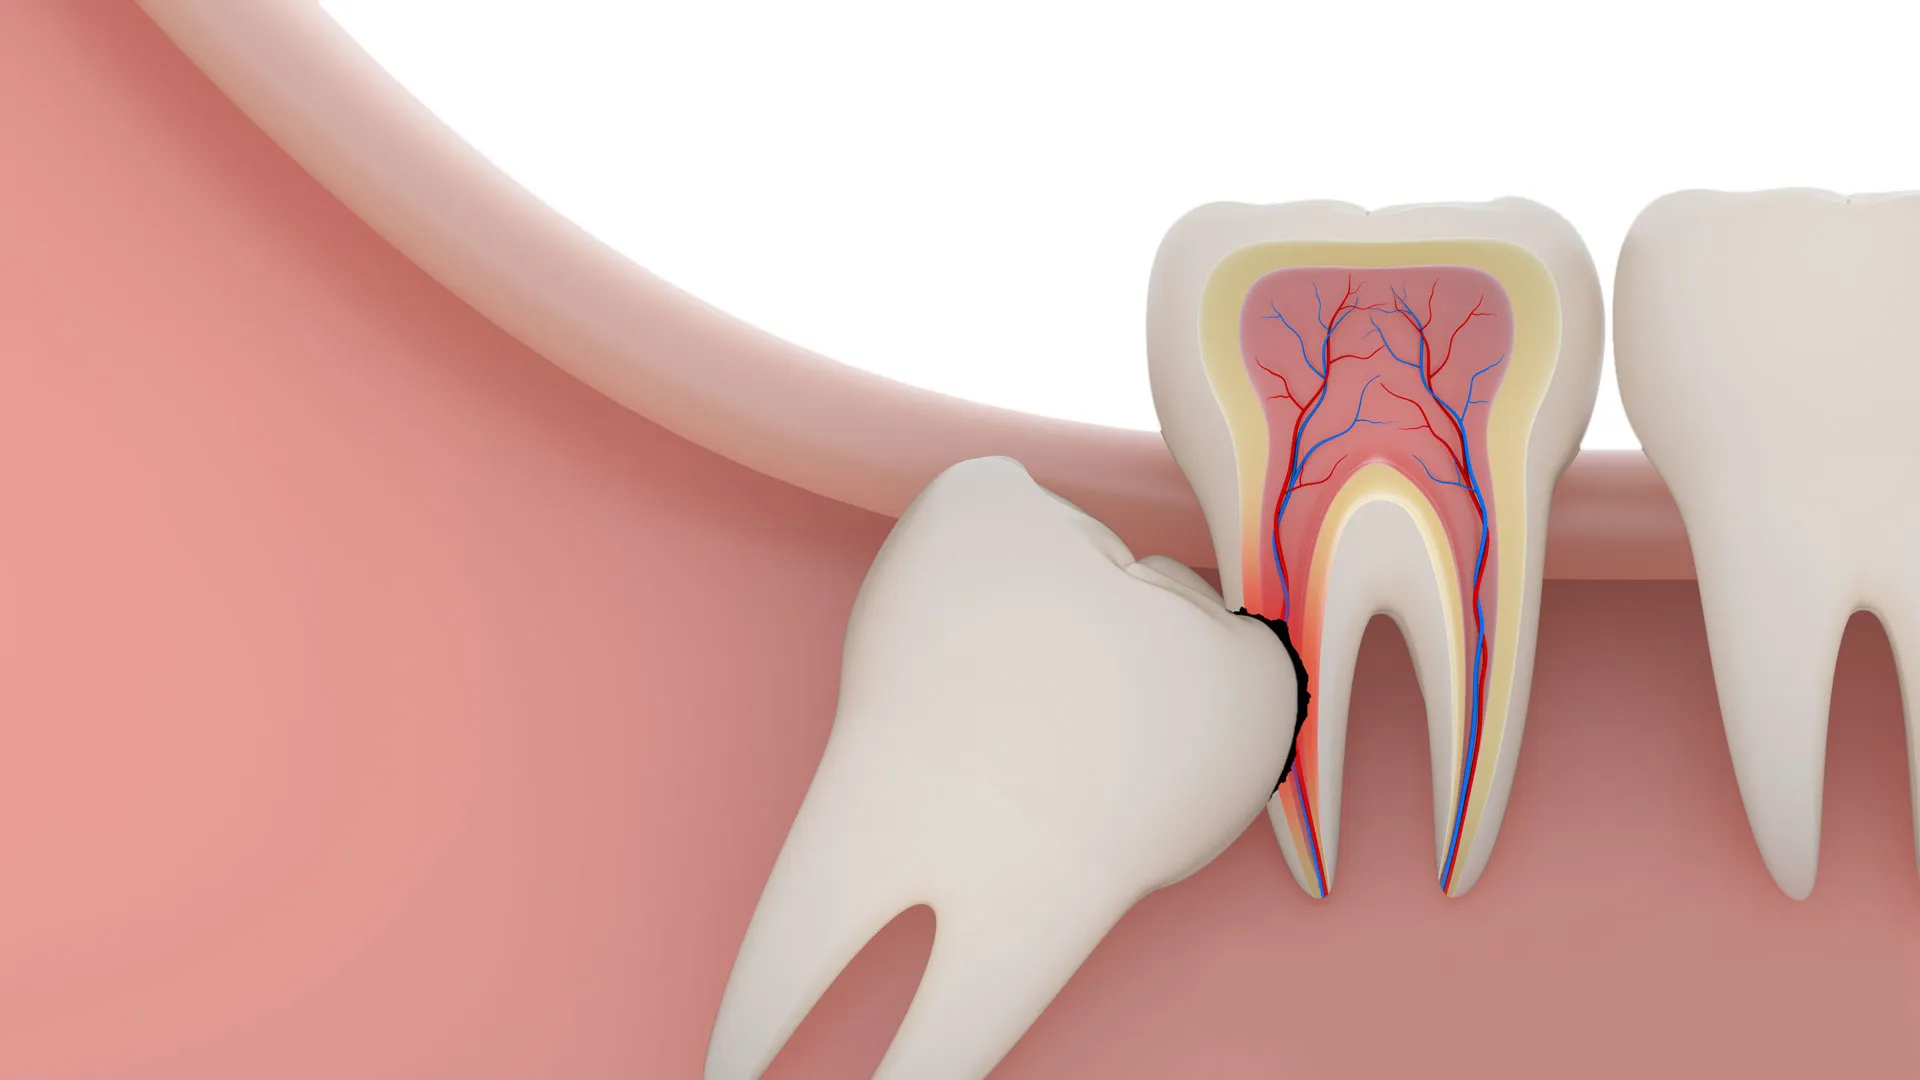

Răng khôn là chiếc răng hàm lớn thứ ba, mọc ở vị trí cuối cùng của cung hàm. Do mọc muộn, khi xương hàm đã ngừng phát triển và trở nên chật chội, răng khôn thường thiếu chỗ để mọc thẳng. Điều này dẫn đến nhiều vấn đề phiền toái.

• Mọc lệch, đâm vào răng số 7 phía trước: Khiến răng số 7 dễ bị xô lệch, hỏng hóc và mất chức năng.

• Mọc ngầm trong xương hàm: Răng không trồi lên được mà bị giữ lại dưới nướu, gây đau nhức âm ỉ.

Răng khôn là chiếc răng hàm lớn thứ ba, mọc ở vị trí cuối cùng của cung hàm

Chính vì vậy, răng khôn rất dễ gây ra các biến chứng nguy hiểm như viêm lợi trùm, sâu răng số 7, hôi miệng hay nặng hơn là hình thành nang xương hàm. Tất cả những điều này lý giải vì sao răng khôn bị coi là “rắc rối muộn màng” trong đời sống răng miệng.